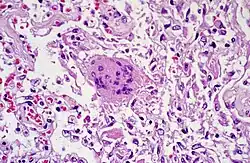

- TOUTON-Riesenzelle - Schaumzellen, bei denen um eine kleine schaumfreie Insel mehrere Kerne ringförmig angeordnet sind, Vorkommen z.B. bei juveniler Xanthogranulomatose, siehe Abb.